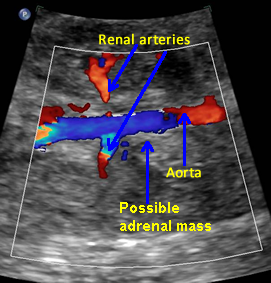

Possible Adrenal Mass

Above. Coronal view. Color Doppler identifies possible mass in region of adrenal gland.

Above. Coronal view. Again, discrete appearing intra-abdominal mass, potentially of adrenal origin.

Above. Longitudinal view. Appearance continues to suggest mass, but follow-up ultrasounds demonstrated resolution of the findings.